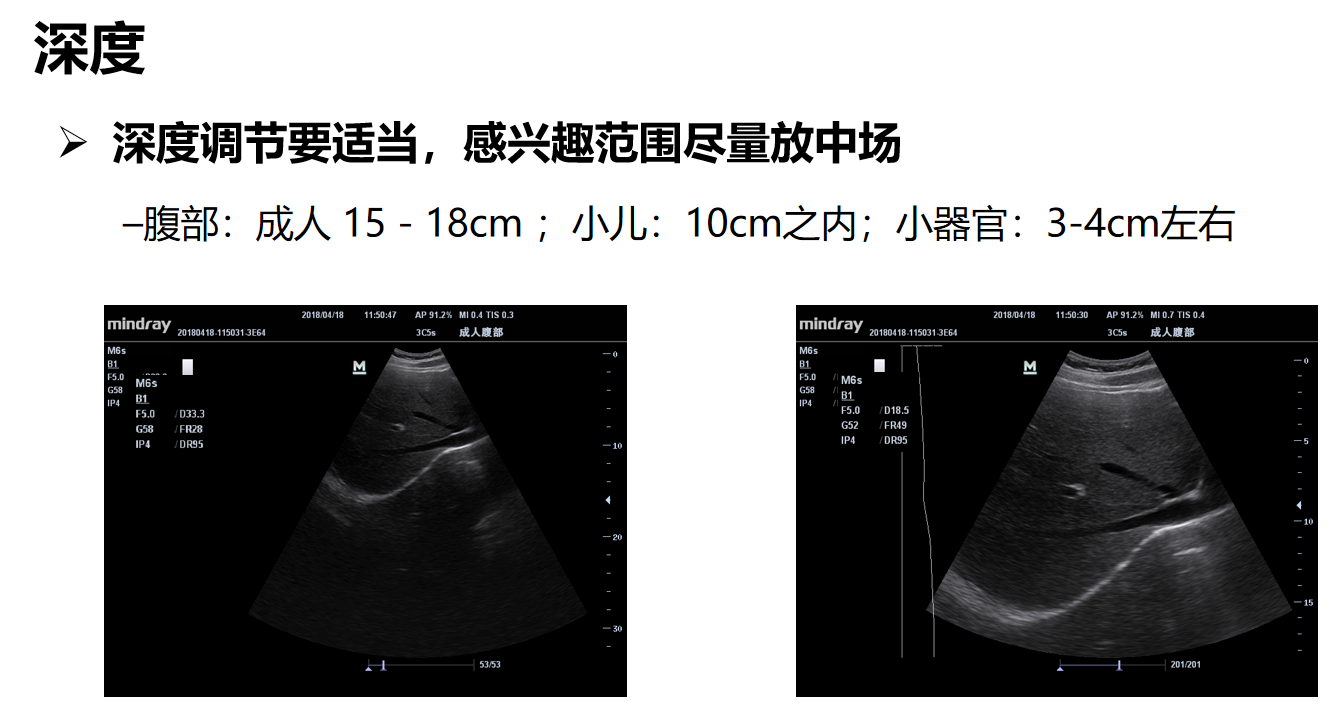

我们先看这两幅图,左边这幅图深度33.3厘米,右边这个18.5厘米,深度越大,观察到的组织越深、范围越大;深度越小,观察到的组织越浅,但是深度越大帧频会越低,深度约小帧频越高。看深度在33.3厘米的时候帧频是28帧,深度在18.5厘米的时候帧频是49帧。帧频会直接影响图像质量,因此为了保证图像质量,在目标区显示允许的情况下使用最小的深度。

一般情况,成人腹部和心脏在15 - 18cm左右;小儿腹部在10cm之内;小器官在3-4cm左右。